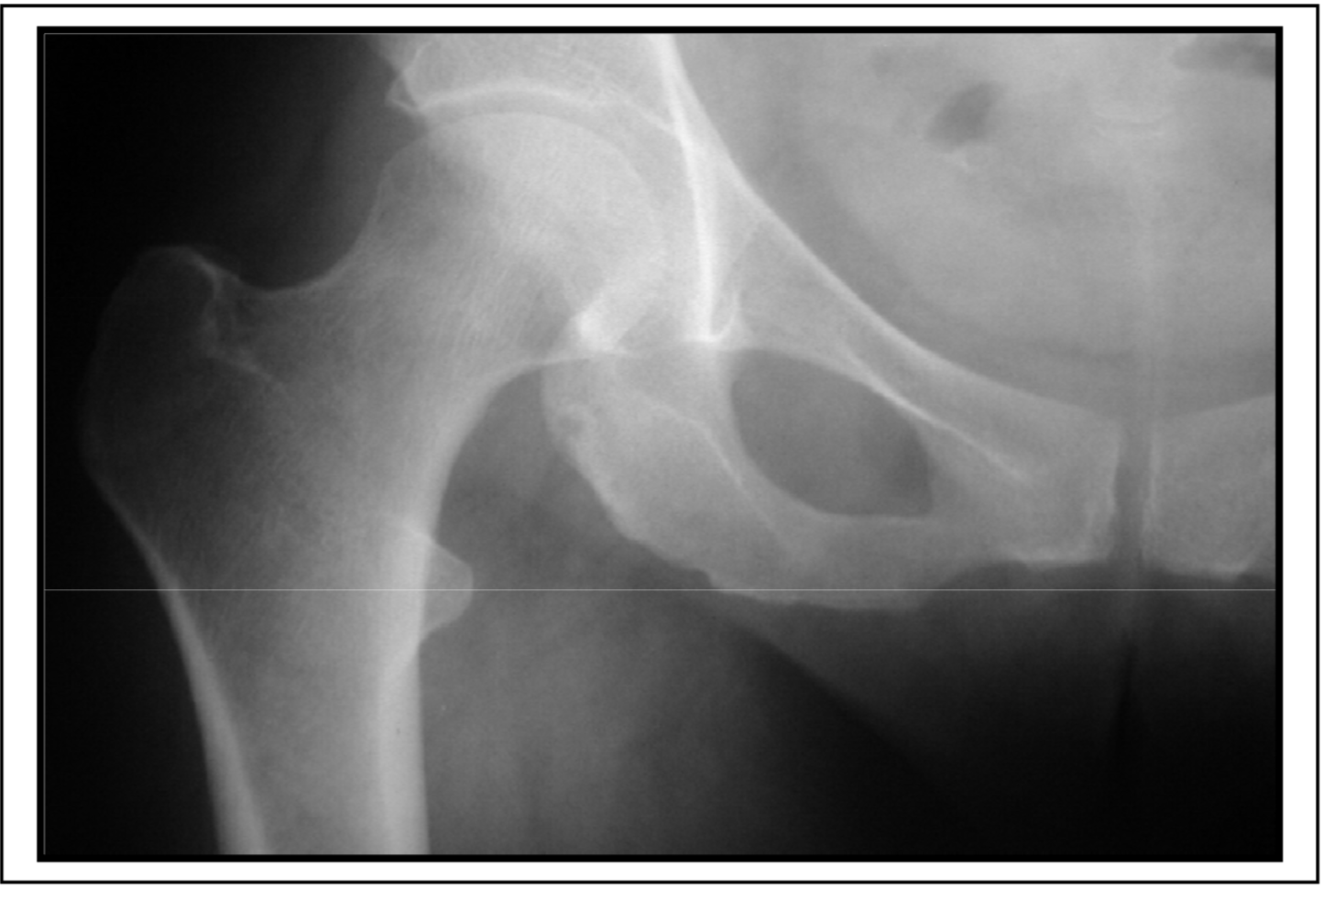

Synovial herniation pit or Pitt’s pit

variation anat normal

Developmental dysplasia of the hip

déformation